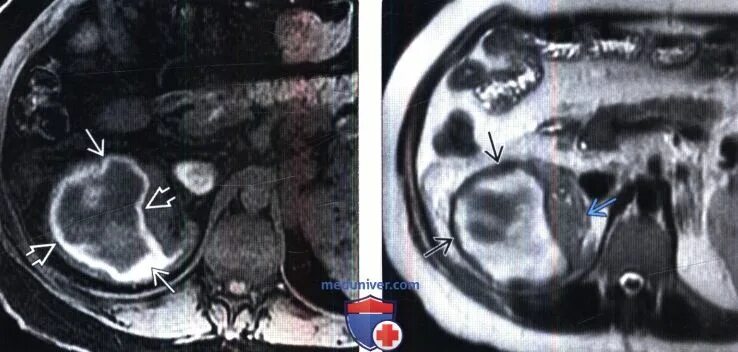

Что входит в мрт забрюшинного пространства